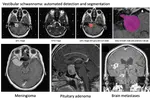

Recently, we organized a Public and Patient Involvement (PPI) group with Vestibular Schwannoma patients to understand their perspectives on an patient-centered automated report. Partnering with the British Acoustic Neuroma Association (BANA), we recruited participants by circulating a form within the BANA community through their social media platforms.

CAI4CAI members and alumni are leading the organization of the new edition of the cross-modality Domain Adaptation challenge (crossMoDA) for medical image segmentation Challenge, which will runs as an official challenge during the Medical Image Computing and Computer Assisted Interventions (MICCAI) 2023 conference.